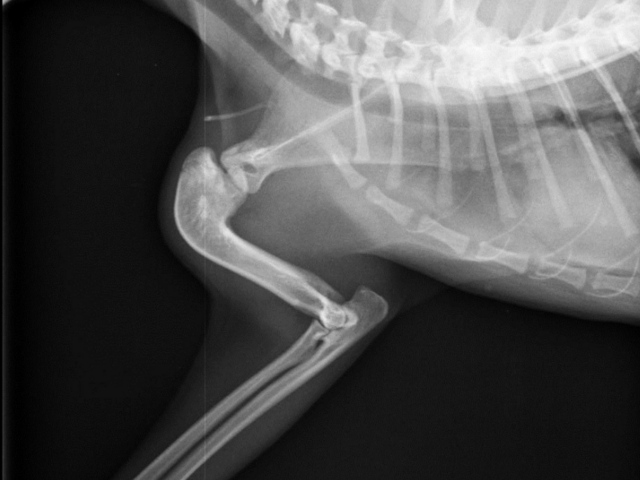

Die Röntgenuntersuchung beim Fachtierarzt für Chirurgie in Weiterstadt ergab, dass bei Ariel eine angeborene Missbildung vorliegt. Der rechte Oberarmknochen hat eine L-Form und zeigt nach hinten. Auch sind die Gelenkflächen nicht normal ausgebildet. Das führt dazu, dass Ariel die rechte Schulter nicht strecken und dadurch nur ganz gebückt laufen kann. Durch diese permanente Fehlhaltung ist leider auch das linke Schultergelenk luxiert (der Oberam luxiert nach außen und vorne). Ariel hat eine ganz schiefe Rückenlinie und die Prognose wäre nicht gut, wenn man nichts tut.....

Ariels deformierter rechter Oberarmknochen, der eine L-Form hat und nach hinten zeigt: